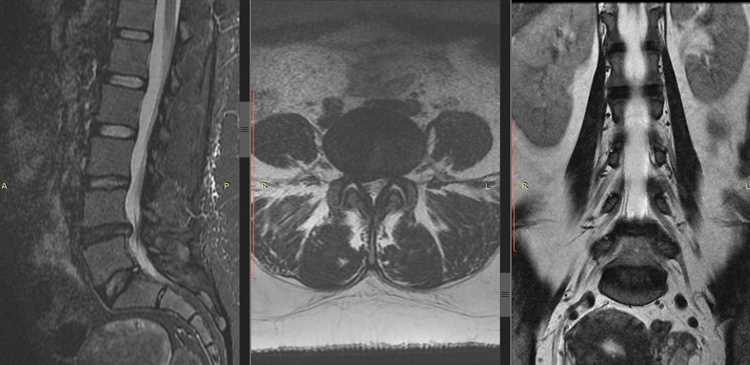

Что категорически нельзя делать при грыже позвоночника?

При грыже позвоночника категорически нельзя игнорировать боль и заниматься физической активностью, которая может усугубить состояние, например, поднимать тяжести, выполнять резкие движения или заниматься спортом без предварительной консультации с врачом. Также следует избегать длительного сидения и неподвижности, что может привести к ухудшению симптомов.